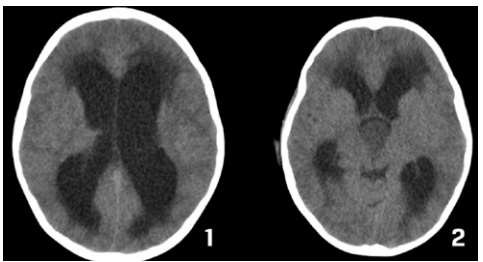

Caso clínico 3 para as questões 27 e 28.

Criança feminina, 04 anos, é encaminhada de Unidade de Pronto Atendimento (UPA) de Olinda-PE com história de cefaleia acompanhada de vômitos, inapetência e sonolência há 03 dias, sendo solicitado parecer da neurocirurgia. Ao exame: ECG Pediátrica de 13 (Resposta Ocular = 3 + Resposta Verbal = 4 + Resposta Motora = 6), isocórica e RFM lentificado bilateralmente, mobilizando todos os membros e reflexos presentes e simétricos.

Seguem, abaixo, as imagens de TC de crânio sem e com contraste da paciente, com índice de Evans de 0,41.

Como se calcula o índice de Evans que foi de 0,41 e o que se fazer pela urgência nesse caso, respectivamente?